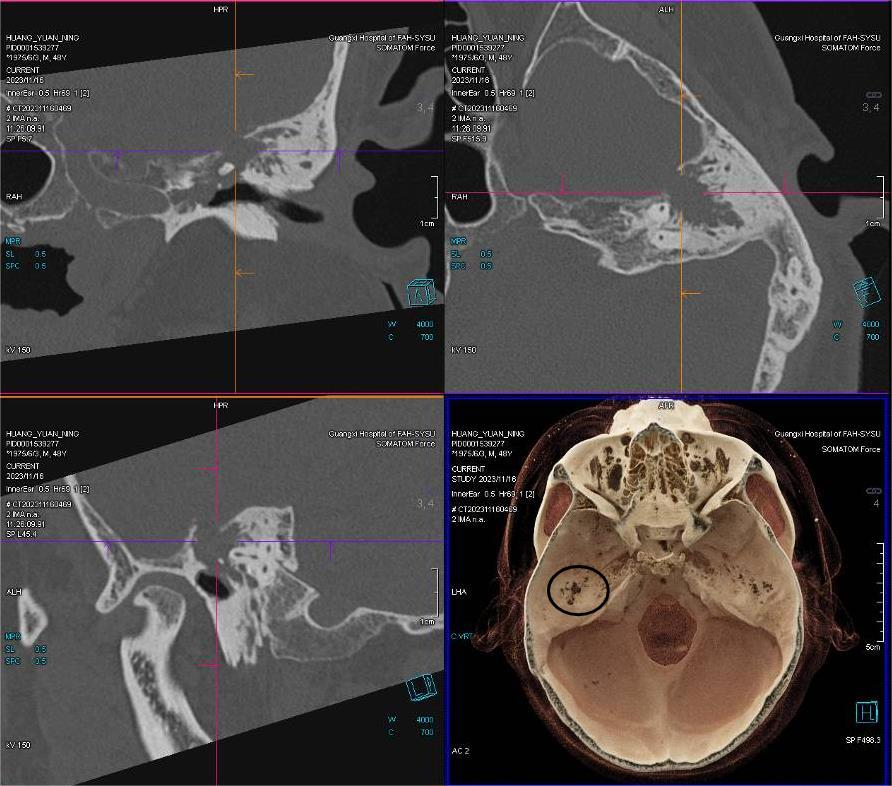

▲CT三维重建显示脑脊液耳漏缺损部位及大小(黑色圆圈示左侧中颅底缺损)。